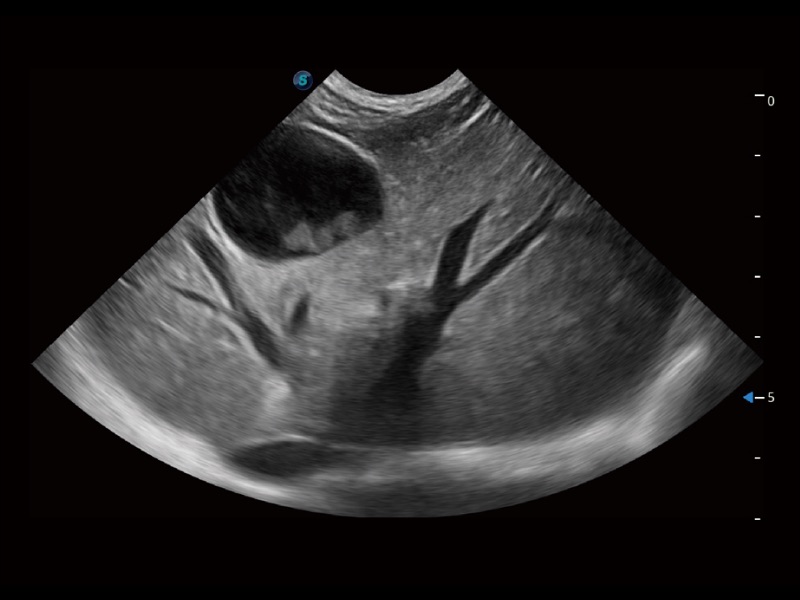

优异的基础图像

(猫)胆囊

(犬)肝脏